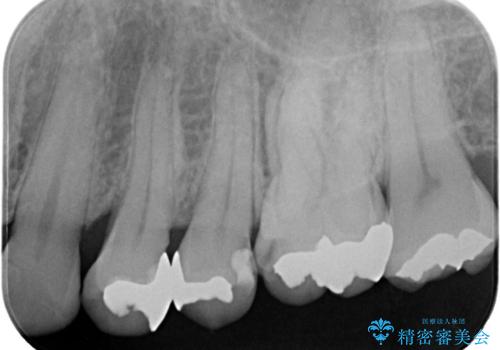

- 歯に穴が開くような虫歯があり銀歯の適合も悪く虫歯になっていたので、虫歯を除去後オールセラミッククラウンで治療を行いました。

左上5、6番の間に隙間もあったのでオールセラミッククラウンで隙間も閉じました。

歯に穴が開くような虫歯があり、銀歯と歯の堺に隙間があり(適合が悪い)そこが虫歯になっていたので適合良く(歯と被せ物の間に隙間が無い)作れるオールセラミッククラウンで治療を行いました。